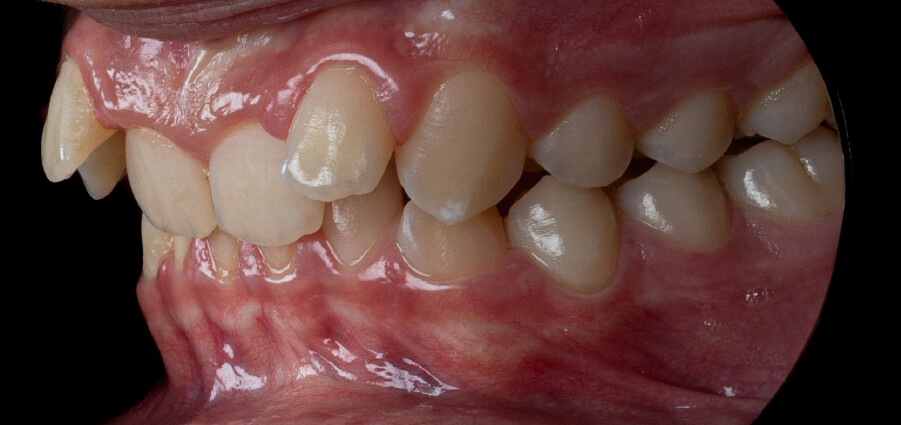

Um paciente do sexo masculino, com 13 anos de idade, apresentou-se com uma mordida profunda, caracterizada pela cobertura quase completa dos incisivos mandibulares. A avaliação clínica revelou apinhamento em ambas as arcadas, rotações dentárias e proclinação dos incisivos laterais superiores, contribuindo para as preocupações estéticas do paciente. O perfil facial era retrusivo, consistente com retrognatismo mandibular, e não foram detectadas anomalias periodontais significativas.

DIAGNÓSTICO:

O paciente apresentava uma relação esquelética de Classe II com molares e caninos bilaterais em Classe II e um padrão dentário de Classe II divisão 2. A mordida profunda estava associada a um apinhamento anteroinferior e a uma curva de Spee acentuada. A análise facial revelou boa simetria, um terço facial inferior ligeiramente aumentado e um perfil convexo caracterizado por retrusão mandibular e do mento. A competência labial estava ligeiramente reduzida, com diminuição do ângulo nasolabial e leve tensão do músculo mentoniano, fatores que comprometiam a harmonia facial global.